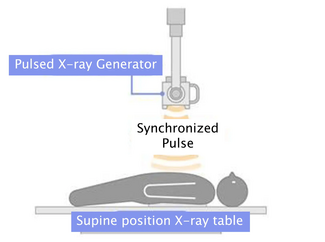

Therapy with 325 mg aspirin, loading 600 mg clopidogrel, and 5.000 IU unfractionated heparin was started, and the patient was immediately transferred to the catheterization laboratory. Coronary angiography showed total occlusion of mid left anterior descending (LAD) coronary artery, with thrombolysis in acute myocardial infarction (TIMI) 0 flow as shown in Figure 2. After vessel  wiring through an Extra Back Up 6 Fr guiding catheter (Medtronic), an aspiration catheter (6 Fr Export AP; Medtronic) was inserted. The blood clot was successfully aspirated with immediate relief of pain and resolution of ST segment elevation. TIMI III flow was restored with no residual lesions at the site of thrombus or the distal parts of the vessel (Figure 3). A decision was made not to deploy a balloon or a stent in the affected area. Left circumflex and right coronary arteries were normal, as detected 1 year before.

A transthoracic echo followed by transesophageal echo obtained after the coronary procedure in the coronary care unit showed a 2.5 cm visible movable thrombus over the atrial surface of the mechanical mitral valve (Figure 4), and almost normal systolic left ventricular function with mild apical hypokinesia. Levels of troponin T and CK were actually raised up to 4.8 ng/mL and 900 IU/L, respectively. The patient was commenced on heparin continuous IV infusion, and a cardiothoracic reintervention was performed 1 week later, confirming the existence of a voluminous thrombus over the prosthetic mitral valve and proceeding in a replacement of the thrombosed valve. Although surgery was technically considered high risk due to a recent history of MI, considerable valve thrombus burden discouraged other non-surgical approaches. Actually, 6 months later, the patient is asymptomatic with normally functioning mitral valve prosthesis.

Coronary embolism usually affects the left coronary system, particularly the LAD. Pesendorfer et al,4 using an in vitro model, found that embolism happens due to active suction of blood/thrombus into the coronary artery at the onset of diastole, at the level of aortic valve. Since the left coronary artery is larger than the right one, a greater proportion of flow is received by the left one, hence, more emboli. Because of the direct downward course of the LAD, it may be more liable to embolization than the left circumflex artery, which is at a right angle to the main trunk.5 In our case, the patient had a totally occluded LAD, and we confirmed the mitral valve as the source of embolus (Figure 4). In all previously reported cases,6-8 a source of embolus was not evident, making the diagnosis of embolic acute MI rather presumptive.